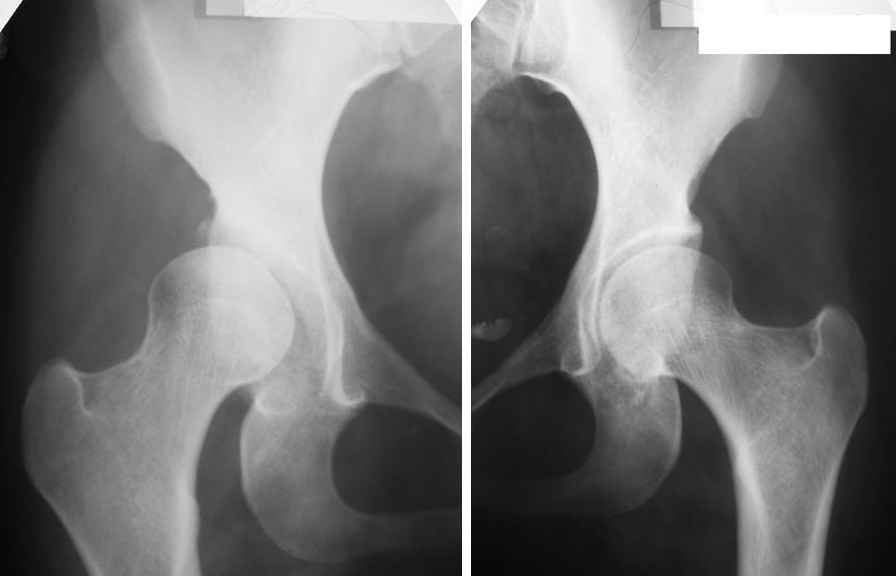

Женщина, 26 лет.

Врожденный вывих обоих бедер, сколиоз грудопоясничного отдела позвоночника 1-2 ст.

С февраля сего года отмечает периодические умеренные боли в правой паховой области. Движения в суставах не ограничены. Больной рекомендовано консервативное лечение.

Справа имеет место подвывих, который далее неминуемо будет нарастать не смотря на профессию. Имеет смысл раннее эндопротезирование в течение 6 месяцев - 1 года. Не стоит ждать проблем со стороны левого ТБ сустава и поясничного отдела позвоночника. Слева по моим приблизительным измерениям угол Виберга около 20 градусов что конечно не достаточно, но при наличии эндопротеза справа с операцией можно будет подождать не один год. ИМХО